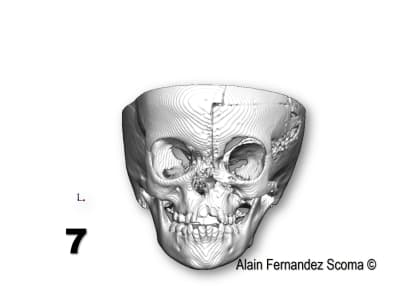

Tien un exemple d'une commande par un Professeur en maxillo- qui me demande : " Alain, tu peux étudier comment segmenter ce massif facial (1) pour reconstruire une forme correcte (2)". Le jour de chirurgie (3) ils sont utilisé un guide de coupe (4)pour tracer les segments et découper la calotte crânienne (5)l'arcade orbitaire... et réorganiser (6) les tronçons. Le scan de contrôle (7) superposé sur l'étude (8) montrent la pertinence du partage. Il y a une découpe dont le tracé à était modifié par rapport à l'étude ce qui m'a fait plaisir de voir justesse d'analyse du chirurgien.